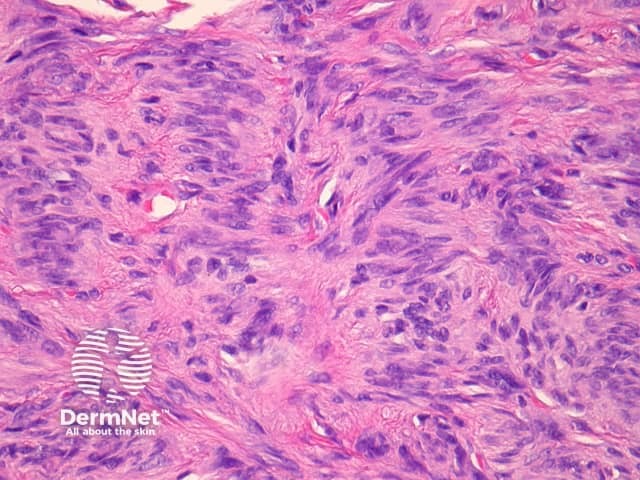

Compared with usual dermatofibroma, cellular dermatofibroma has an increased chance of recurrence following excision and metastasis is reported. Histologically, there is increased cellularity with a swirling, storiform pattern (figures 3,4). Peripheral entrapment of collagen is less prominent in this variant. There may be increased mitoses and extension to the subcutaneous fat, which are associated with more aggressive behaviour. Approximately 10% of cases show central necrosis.

Cellular dermatofibroma may resemble dermatofibrosarcoma protuberans, which can be differentiated by its larger size, increased mitoses and marked involvement of the subcutis. CD34 is positive in dermatofibrosarcoma protuberans and is usually negative in dermatofibroma, although the cellular variant may have focal positivity, especially at the periphery of the lesion. A study of clonal karyotype abnormalities in dermatofibroma found cellular dermatofibromas were more likely to have karyotype abnormalities than common dermatofibromas.

Figure 3

Figure 4